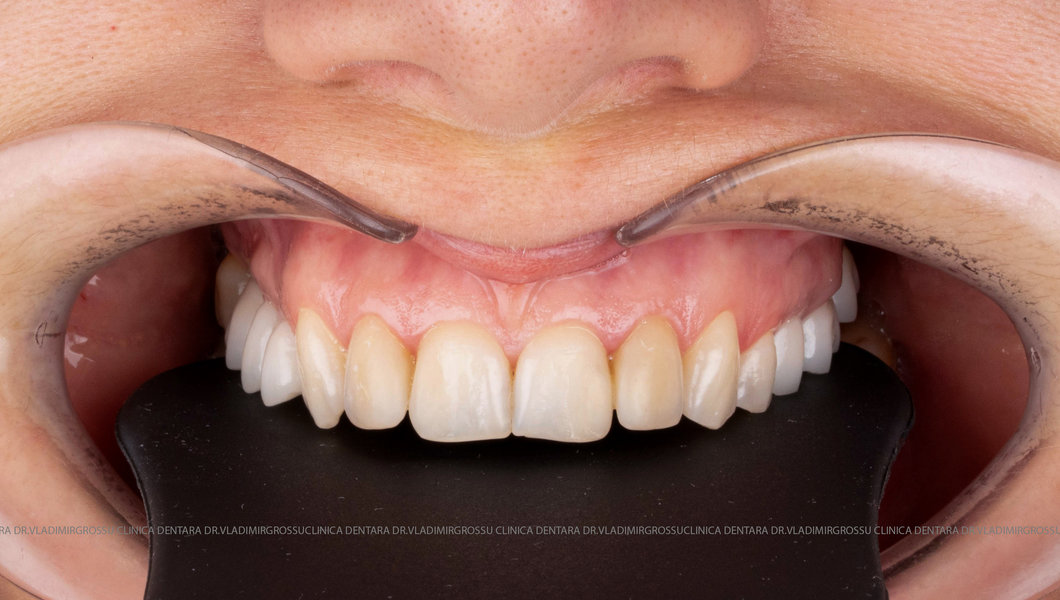

Caz 1

Designul noului zâmbet

În cazul în care pacientul pune la dispoziție fotografii vechi, acestea sunt analizate, însă adesea reabilitarea presupune crearea unui zâmbet nou, personalizat. Pacienții adesea au preferințe clare privind forma și aspectul dinților viitorului zâmbet, iar echipa medicală depune toate eforturile pentru a le respecta dorințele. Dacă este cazul, se propune un design alternativ, explicat pe larg pacientului, care, de regulă, îl acceptă. Protocolul foto-video este indispensabil pentru realizarea unor astfel de lucrări.